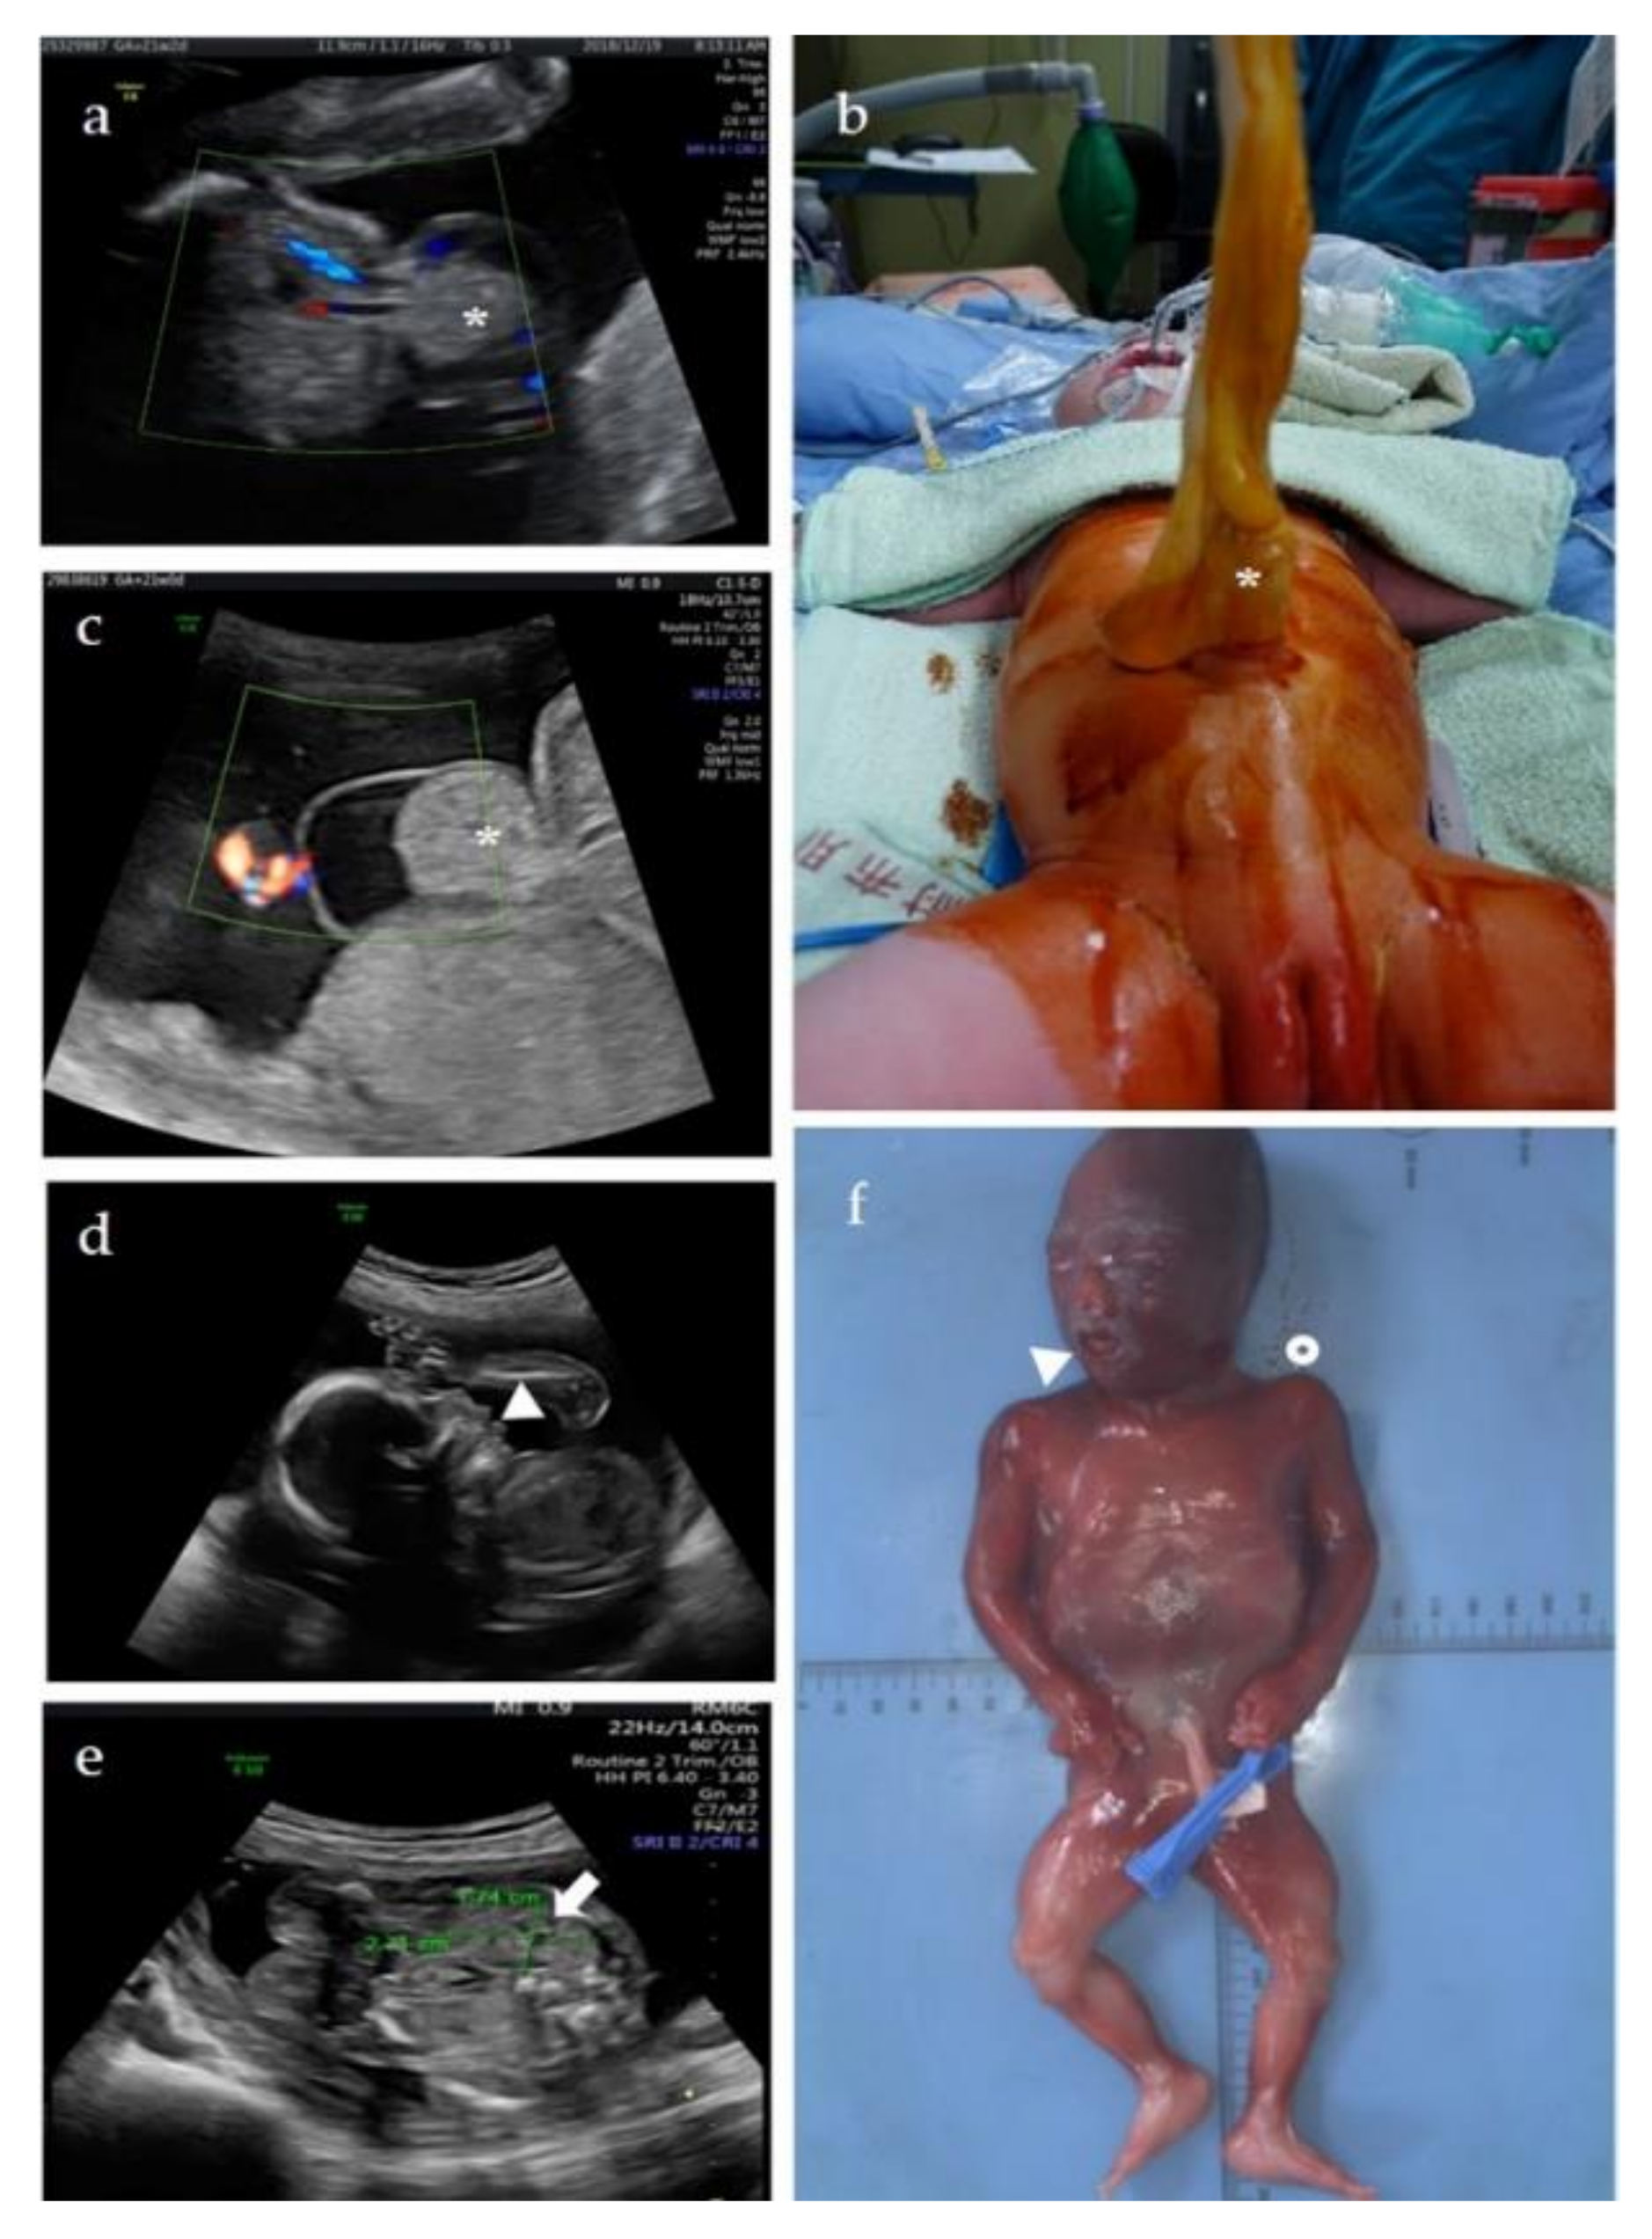

3.1.1. Patient 1

3.1.2. Patient 2

3.1.3. Patient 3